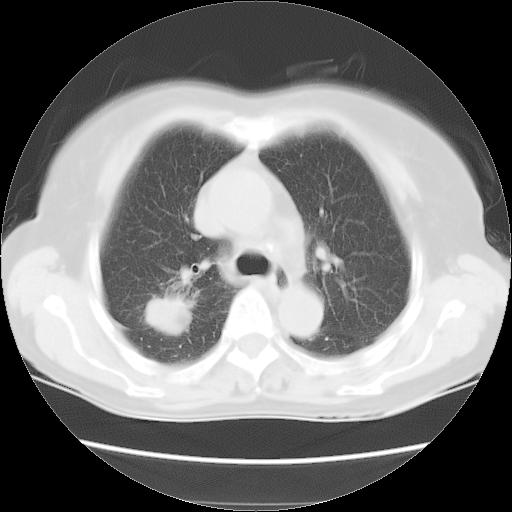

以下是引用夏季在2007-9-18 11:00:00的发言:[br]1。右肺肿块,周围有短毛刺,肺门侧有血管与其相连,胸壁侧有胸膜凹陷征,考虑周围性肺癌 2。左侧甲状腺软组织肿块,内有高密度钙化灶,考虑左侧甲状腺腺瘤。

以下是引用卜一在2007-9-18 14:41:00的发言:[br]右肺肿块:毛刺+胸膜凹陷征+供血血管+浅分叶+强化。支持:周围性肺癌 !另:左侧甲状腺腺瘤!